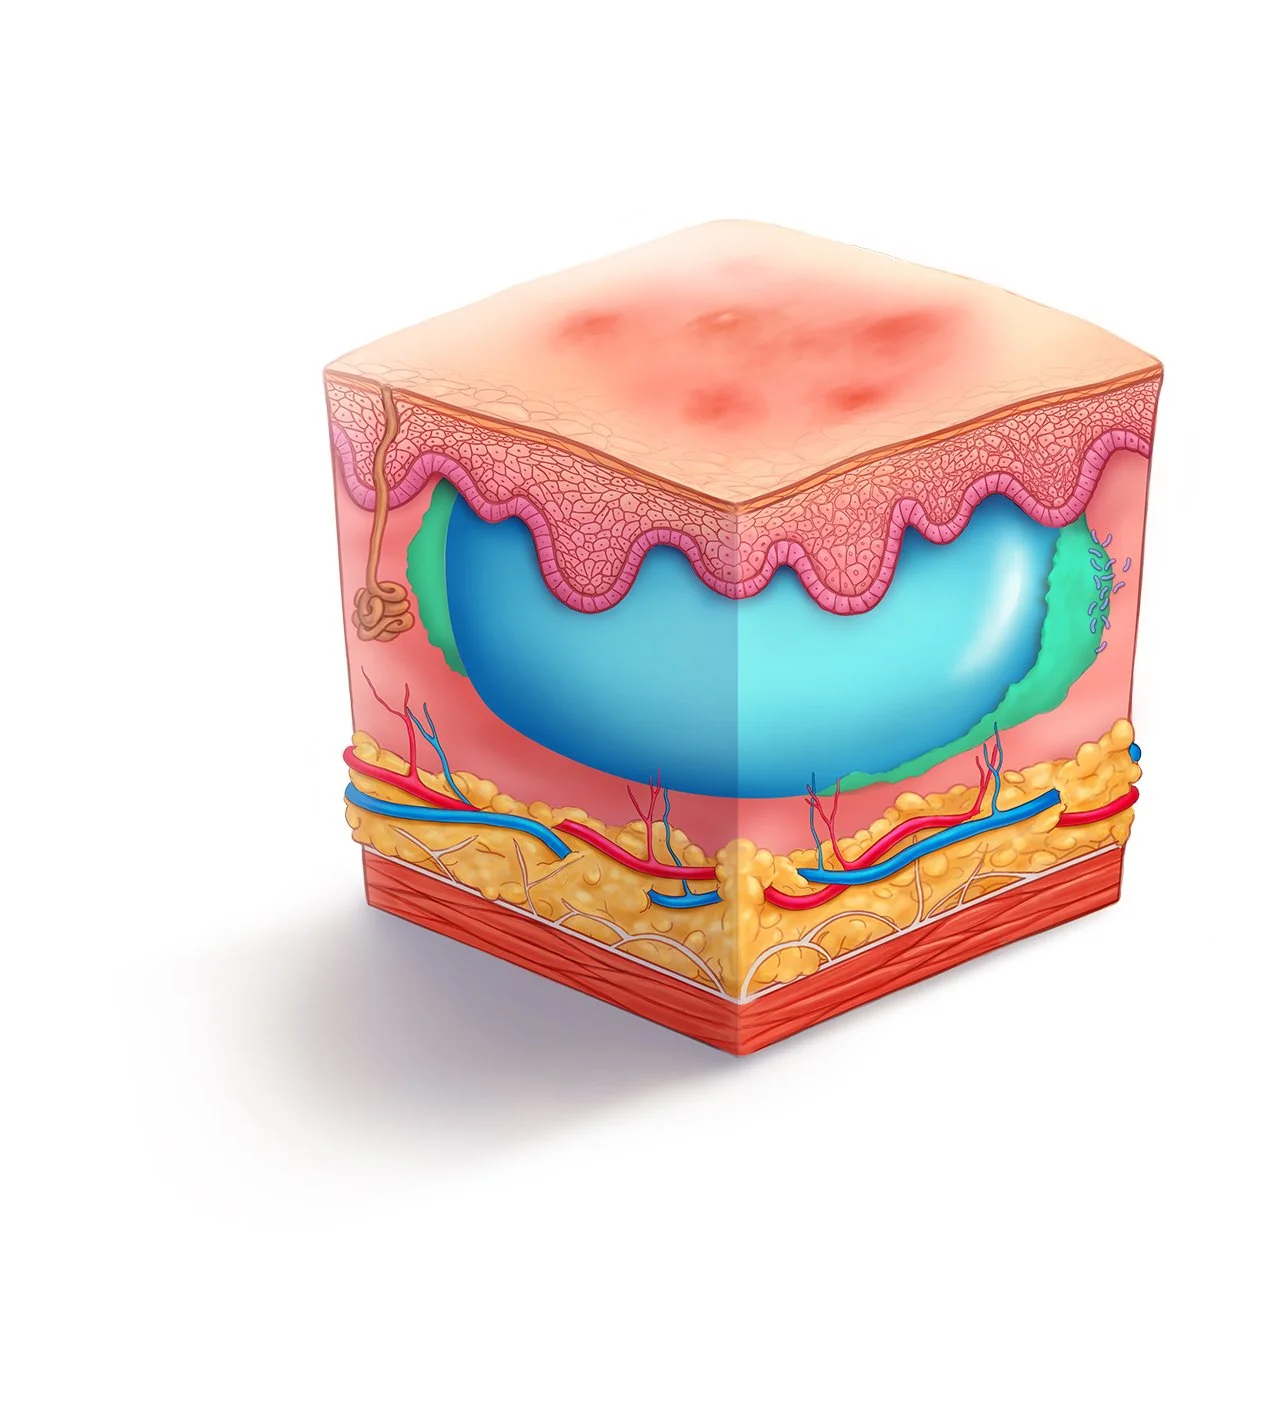

We are no strangers to the life sciences. Our medical animations animations can show how molecules interact in the body, how surgical procedures are performed, or how a new drug works at the cellular level. These visual aids help healthcare professionals, researchers, and patients understand complex medical concepts and procedures more easily.

We specialize in a wide variety of medical visual communications. Take a closer look:

Medical Illustration